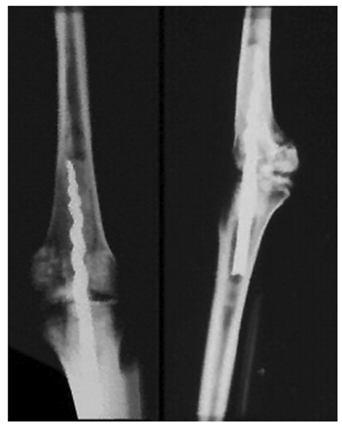

Исторический обзор, проведенный в этой статье, призван обобщить эволюцию интрамедуллярного стержня, выделить его важные вехи, представить атмосферу периода первого использования и последующей эволюции интрамедуллярного стержня, а также представить место интрамедуллярного стержня в современной ортопедии и травматология (например, рисунок 1).

Так было в случае с мумией по имени Усермонту, найденной в гробнице Тутанхамона, где между бедром и большеберцовой костью был вставлен гвоздь с резьбой для стабилизации коленного сустава (как на рис. 2).